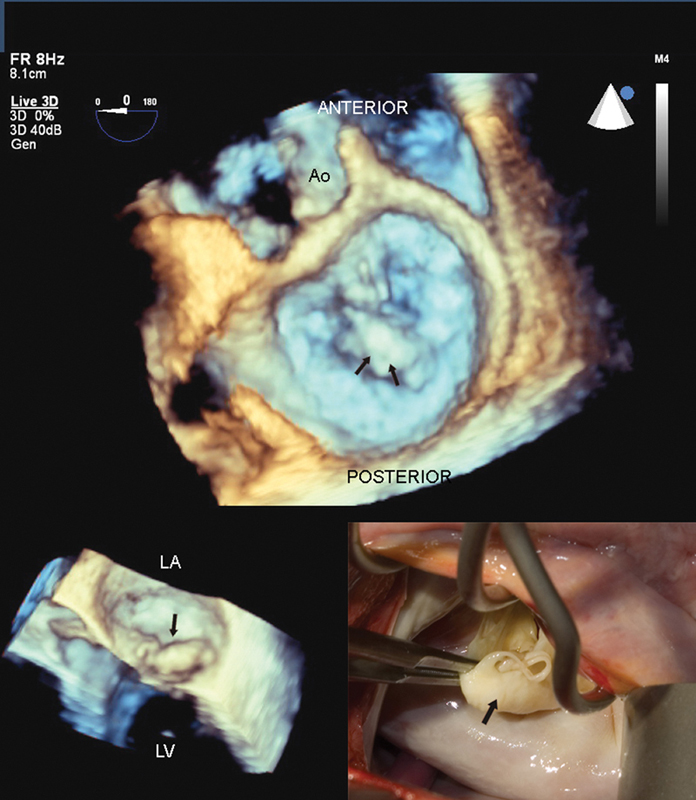

فحوصات تشخيصية لبعض امراض القلب والشرايين التاجية